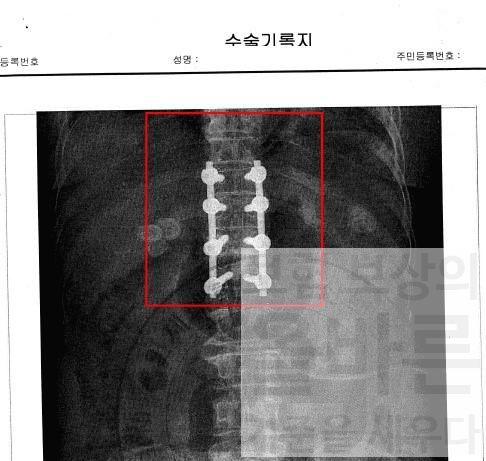

위에서 보는 진단서, 수술기록지 외에도 간호정보 조사지, 영상자료 등

여러 자료를 검토하고 장해진단을 하였어요

수술기록지에서 확인되는 것처럼 척추체 4개에 고정술을 시행하였는데,